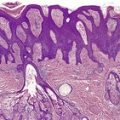

Inflammatory lesions have traditionally been attributed to the accumulation of neutrophils within microcomedones or comedones with subsequent rupture of the follicle and the formation of a pustule in the dermis. It now appears that there is an even earlier stage which involves the transmigration of lymphocytes into the wall of the follicle associated with increasing spongiosis of the follicular epithelium (Fig. 15.1). 171 This change has been likened to an allergic contact sensitivity reaction. 171 This is followed after 24–72 hours by the accumulation of neutrophils within the follicle, leading to its distension and subsequent rupture. 171 There may be a localized loss of the granular layer in the region of the eventual rupture, suggesting a defect in keratinization in this region. A perifollicular pustule develops following the rupture of the comedo (Fig. 15.2). Lymphocytes, plasma cells, and foreign body giant cells subsequently appear. The follicular epithelium tends to encapsulate the inflammatory mass; sometimes this is followed by the formation of draining sinuses lined by remnants of the follicular epithelium. When the inflammatory process subsides, distorted secondary comedones may result.

Acne vulgaris. A perifollicular pustule is present in the dermis. It contains liberated hair shafts. (H & E)